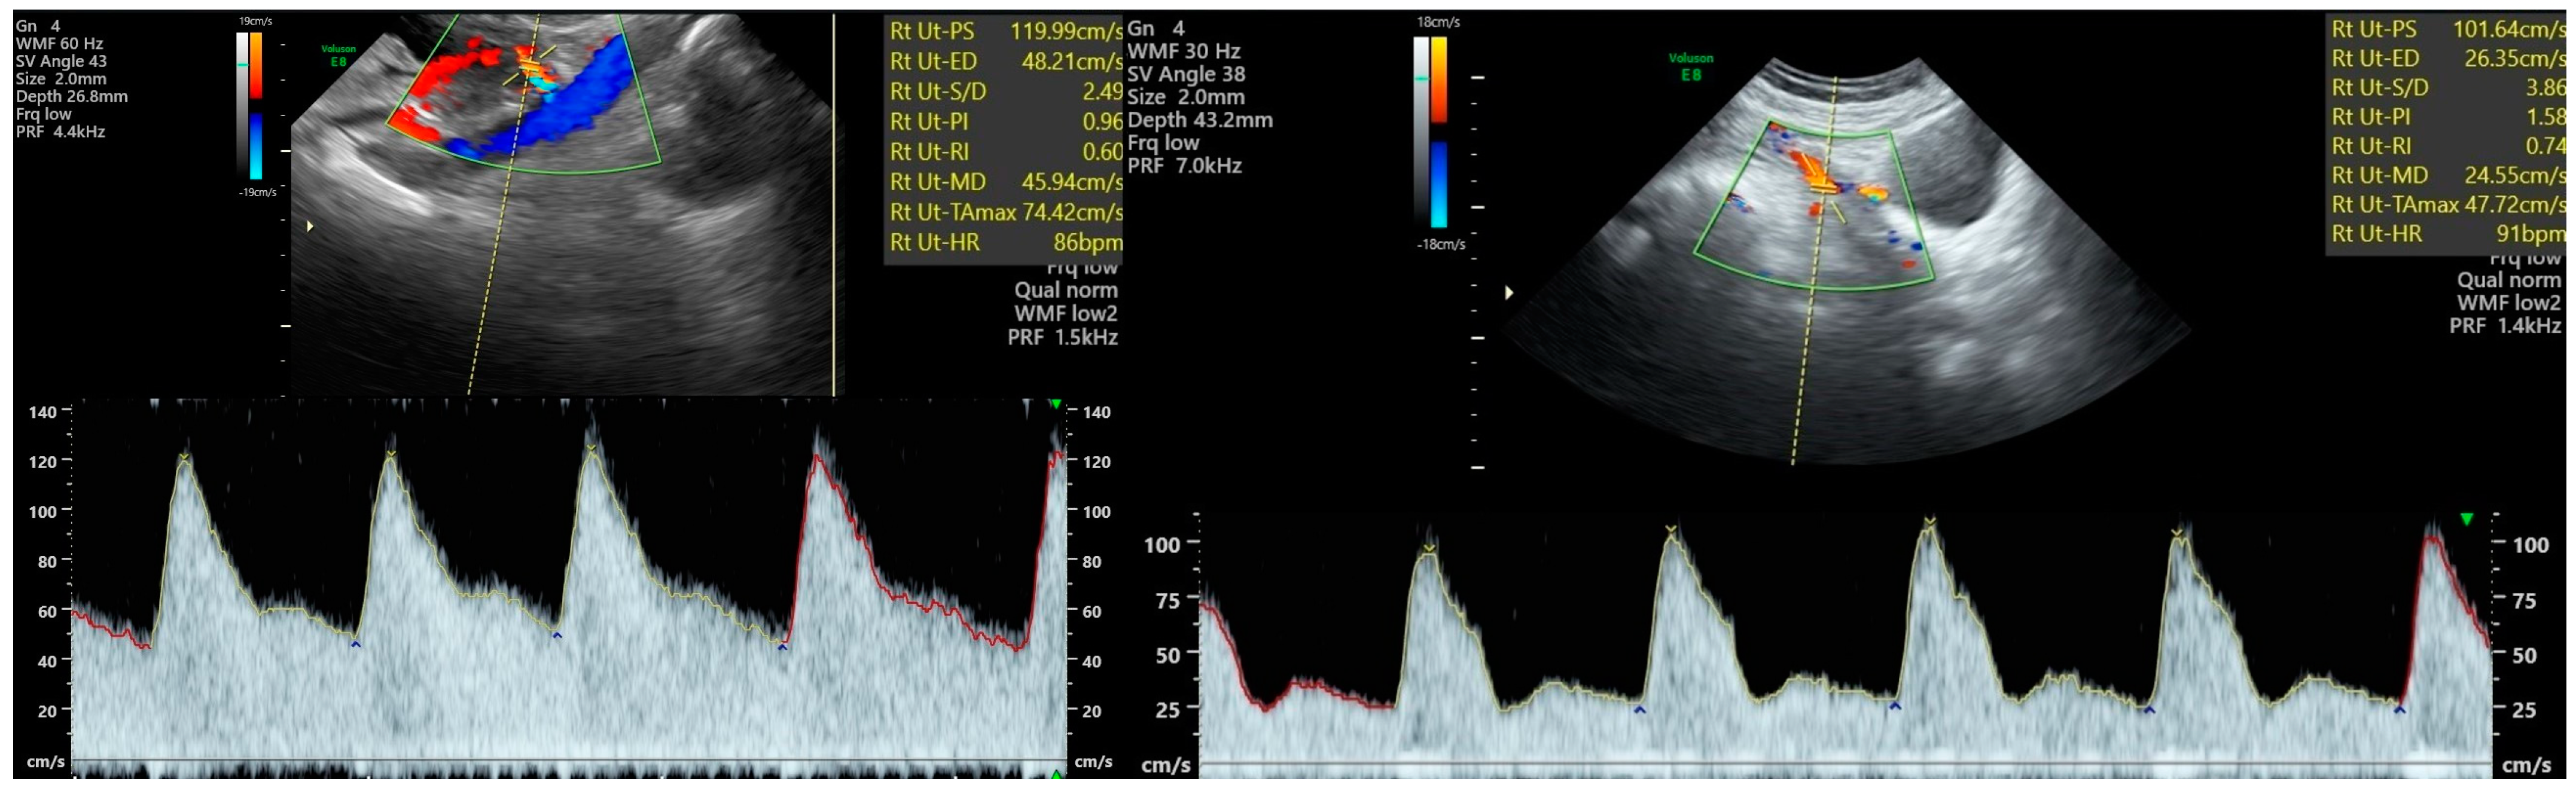

4. Prediction and Clinical Management of Pre-Eclampsia and Other Adverse Pregnancy Outcomes Using Doppler Velocimetry Indices

5. Uterine Artery Doppler—Technique and Reference Parameters